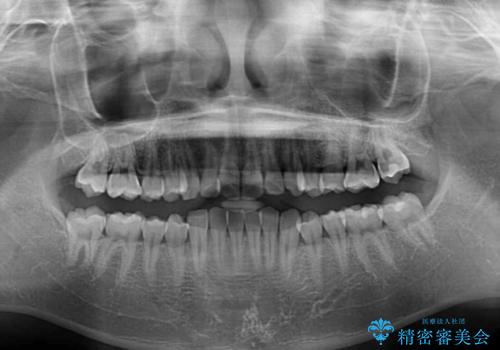

- ディープバイトと上顎前歯の突出、奥歯の咬み合わせを気にして来院された患者様です。

上顎歯列は全体的に前方位にあり、それが原因で深い咬み合わせとなり、突き上げにより上顎前歯が前方に飛び出している状態でした。

また、左右ともに上顎最後臼歯が頬側に転位している鋏状咬合となっていました。

インビザラインによる矯正治療をご希望でしたが、上顎歯列の前方位と鋏状咬合を確実に改善することを目的として、補助装置を併用することとしました。